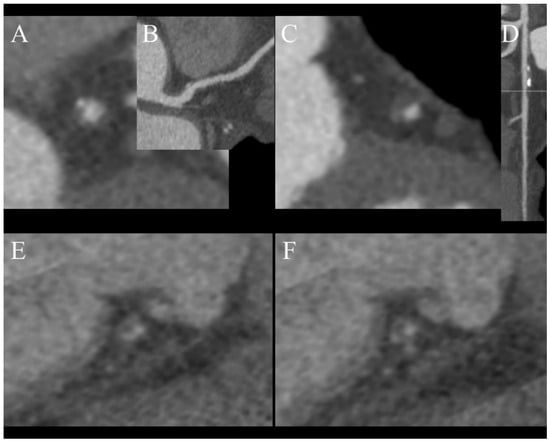

- Spotty calcification (Figure 4A,B);

Figure 4. Features of venerable plaques. (A,B)—spotty calcification—calcification smaller than 3 mm and less than 150% lumen diameter (A)—short axis view, (B)—curved MPR of the vessel; (C,D)—positive wall remodeling—outer diameter of involved section of the vessel at least 110% of non-involved part of vessel; (E,F)—both plaques are noncalcified and low density (<30 HU) corresponding to cholesterol reach core, (F)—napkin ring sign—hyperdense outer part of noncalcified plaque. - Positive remodeling (Figure 4C,D);

- Low density core (Figure 4E,F);

- Napkin ring sign (Figure 4F).

A study by Nakajima et al. determined that using a value of 9.3 as the effective atomic number has 90% sensitivity in distinguishing soft and fibrous plaques, while density with a cutoff value of 55 HU only has 62% sensitivity. A limitation of this study is that it had a small population of just 18 patients [42]. In summary, plaque characterization in DECT has still not been fully researched and requires further investigation, but combining information regarding the effective atomic number with CT features of unstable plaques (Figure 3) can help to determine the nature of atherosclerotic changes in examined vessels [24]. We do not use DECT to characterize plaques in daily practice and rely on CT futures of venerability, which were mentioned earlier.